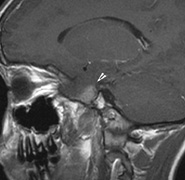

STURGE-WEBER SYNDROME Sturge (1879) reported the case of a child with facial “port-wine stain,” epilepsy, buphthalmos, and a dark choroid.204 Schirmer had noted the association of the facial vascular malformation and glaucoma in 1860.3 Weber (1922) reported brain X-ray findings of parallel streaks (“railtrack” sign), which he interpreted to represent calcific changes (Fig. 19).205

The PWS may not entirely respect the midline, possibly a reflection of transmedian innervation.212 The lesion grows proportionally with the child, often becoming darker in color. 213 The overlying skin may develop nodularity or hypertrophy in two-thirds of patients (by the fifth decade).214 Treatment with a pulsed-dye laser may significantly improve the appearance, but recurrence (i.e., redarkening) is possible.215,216 A deficit in the number of perivascular nerves in port-wine stains suggests that abnormal neural modulation of vascular flow may be involved in their pathogenesis.217 Intracranial leptomeningeal capillary vascular malformation (Figs. 21 and 22) is associated with seizures and contralateral neuromuscular weakness. Central nervous system involvement correlates highly with ipsilateral involvement of the V1 dermatome by a PWS.208,218

It has been hypothesized that the calcific changes reflect cellular anoxic injury secondary to venous stasis/poor drainage.219,220 Abnormal autonomic innervation has also been reported in association with the malformed cortical vessels—innervation only by noradrenergic fibers.221 Studies suggest that the normal increase in brain-blood flow to accommodate increased metabolic demand during seizure activity is blunted in affected brain regions of SWS.222 Thus, seizures in the setting of impaired perfusion may be exacerbating brain injury. Periods of contralateral weakness (days to weeks) can follow a prolonged seizure episode.206,223 When seizures begin early in life, the risk of developmental delay is much higher. In a review of 171 patients with a facial PWS and associated intracranial vascular malformation, 80% were found to have a seizure disorder. Of those, 75% with seizures had an onset during the first year of life, rising to 95% before age 5 years. Nearly all patients had a PWS that included (or was limited to) the V1 distribution. Developmental delay was strongly associated with seizures (71% of children with seizures as compared to 6% without seizures).224 Glaucoma affects 50% to 70% of SWS patients224,225 and it is a therapeutic challenge. From the time of diagnosis, the intraocular pressure, the optic discs, and the corneal diameters need to be measured intermittently, even if an occasional examination under anesthetic is required. The development of glaucoma appears to follow a bimodal age distribution: early-onset/congenital-type and later-onset. The glaucomatous eye is nearly always on the same side as the PWS.224 The highest risk for glaucoma appears to be when the PWS involves both the upper and lower lid: 72% vs. 21% for VI-only (upper eyelid) involvement in one study.224 The bimodal age distribution of glaucoma suggests that more than one mechanism is involved. Angle abnormalities (“trabeculodysgenesis” with or without flat anterior iris insertion) have been reported in association with the early-onset/congential type.225 Other proposed mechanisms include uveal capillary dilation226 and elevated episcleral venous pressure. Reports of blood in Schlemm's canal on gonioscopy support the idea of increased episcleral venous pressure pathomechanics.227,228 Glaucoma in SWS often responds poorly to medical therapy alone. The “trabeculodysgenesis” of early onset Sturge-Webber glaucoma is reported to be similar in gonioscopic appearance to primary congenital glaucoma.229 On this basis, goniotomy was suggested as a treatment of choice in early-onset SWS glaucoma. One group looked at the success of goniotomy, trabeculotomy, trabeculectomy, laser trabeculoplasty and medication in the management of SWS-associated glaucoma.230 In the early onset subgroup receiving goniotomy, median stable interval of intraocular pressure reduction after one procedure was 8 months; with multiple goniotomies and the addition of medical treatment, the median stable interval was extended to 9 years. Other investigators have found that goniotomy alone may be insufficient, requiring filtering surgery at some point. However, trabeculectomy carries a significant risk of choroidal expansion in association with hypotony. Theoretically, the risk may be higher when there is increased choroidal vascularity in association with the facial PWS—a “tomato ketchup” fundus.231 Often, there is associated increased tortuosity of the retinal vessels as well. Placement of a prophylactic posterior sclerotomy prior to filtering surgery to prevent choroidal expansion is controversial.232 Cryo- or thermocoagulation of the ciliary body in combination with medical therapy may be an alternative to surgery.233 KLIPPEL TRENAUNAY—WEBER SYNDROME Klippel-Trenaunay syndrome consists of combined capillary, lymphatic, and venous malformations, in association with varicosities and limb enlargement (Fig. 23). In the majority of cases, the lower limb is affected.234,235